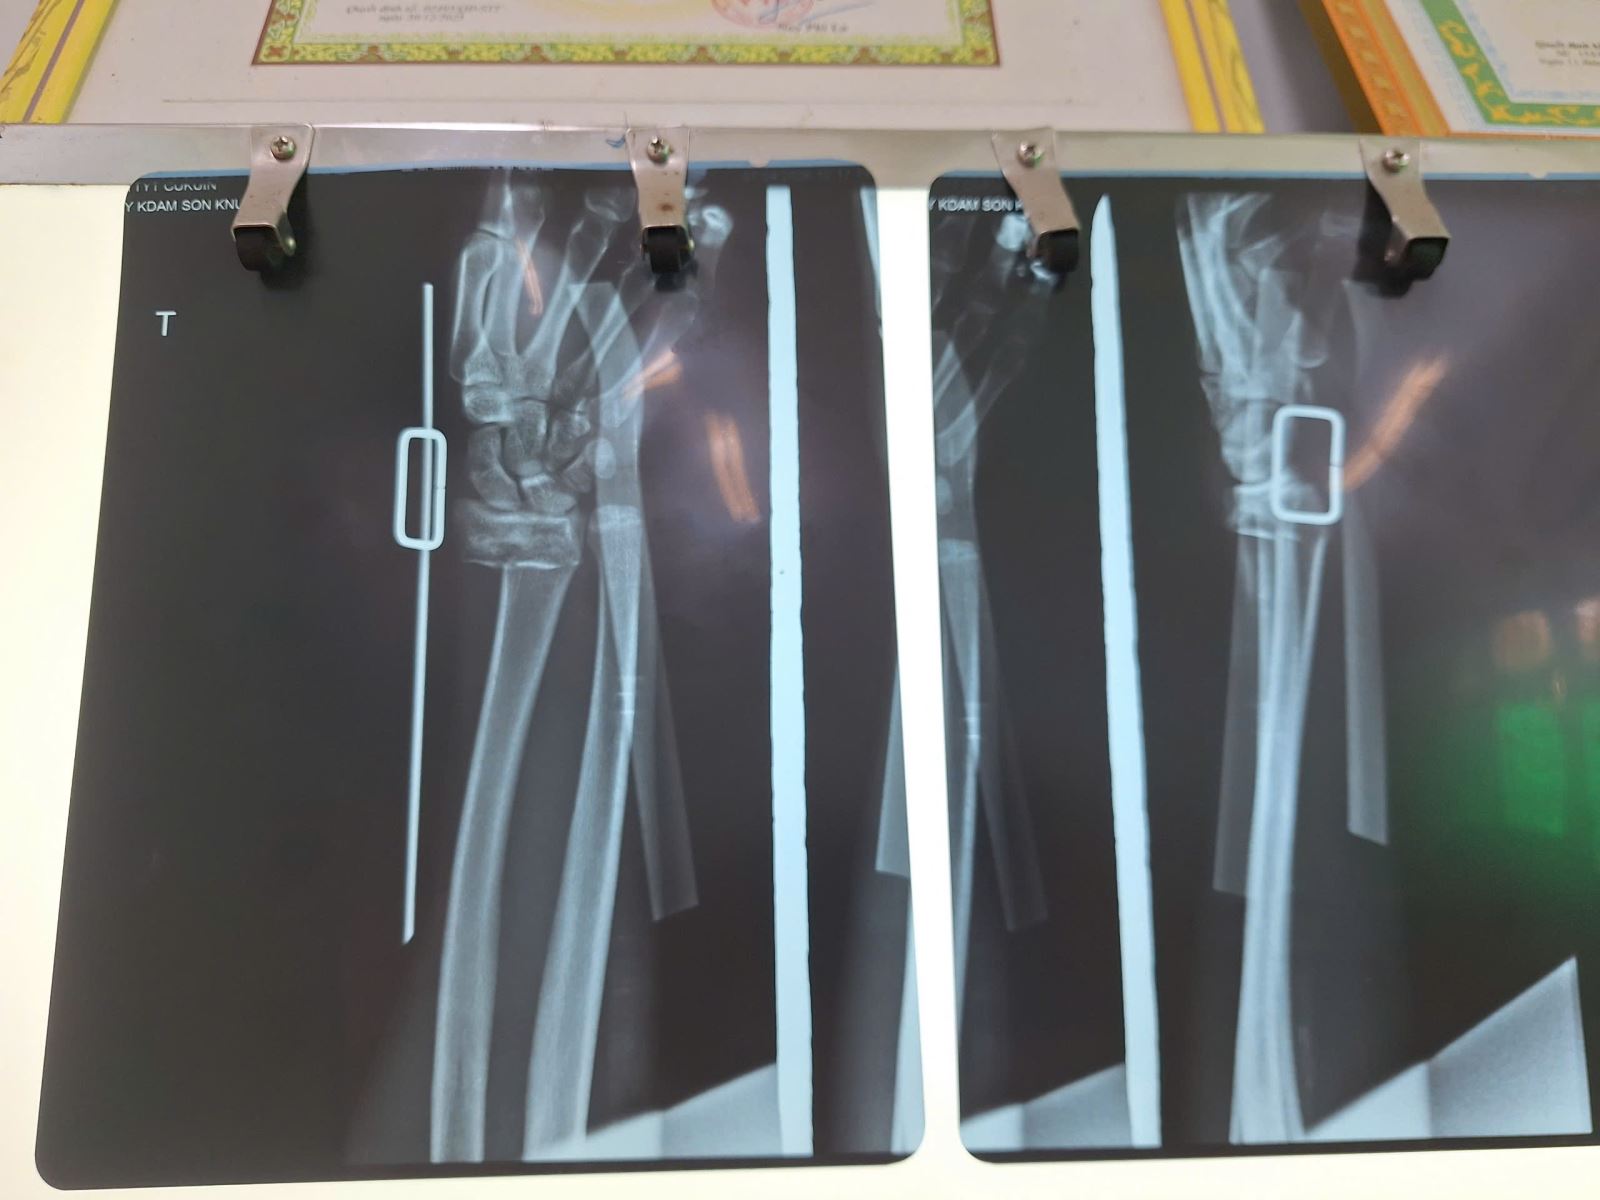

Ngày 8/4/2026 bệnh nhân nam Y.S.BP, sinh năm 2003, Buôn Ea Khít, xã Dray Bhăng, Đắk Lắk vào viện do tai nạn giao thông. Bác sĩ Lê Hùng thăm khám với kinh nghiệm chuyên môn nghiệp vụ bệnh nhân được chẩn đoán: Gãy kín đầu dưới hai xương cẳng tay phải/đa chấn thương do tai nạn giao thông. Ngay sau chẩn đoán bệnh nhân được xử trí nắn, bó bột, theo dõi điều trị tại khoa ngoại, tình trạng hiện tại bệnh nhân ổn định.